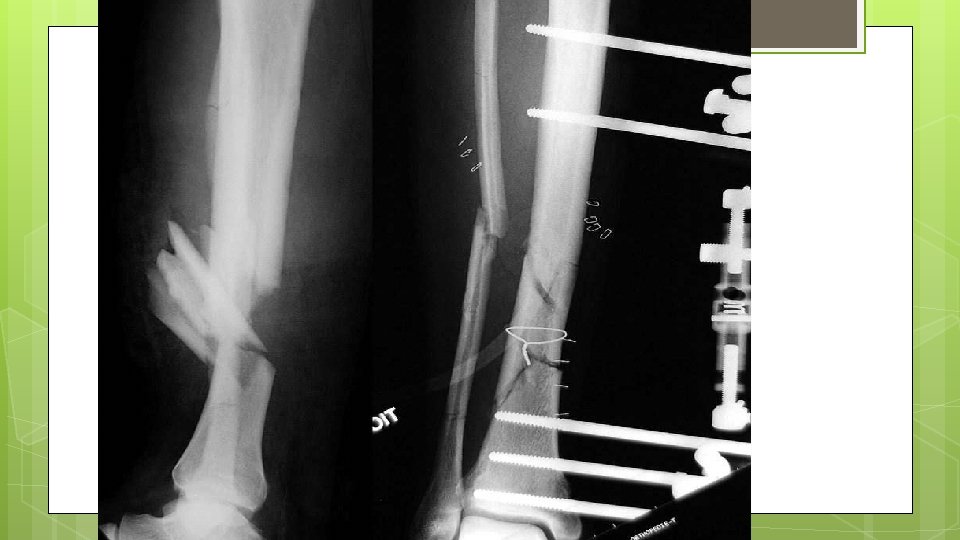

Définition Fixateur externe : Appareil permettant la fixation squelettique de fiches transcutanées, de rotules et de barres d’union a distance de la fracture ou du site opératoire

Urgences chirurgicale s Indications Traumatologie : Fractures ouvertes des os longs avec ou sans perte de substance Fracture avec lésions cutanées Fracture du bassin Fractures compliquées et déplacements secondaires Echec d’oste osynthe se Orthope die : Chirurgie de correction posturale dans le cadre d’Infirmite Moteur Ce re brale (IMC) Extension de membres